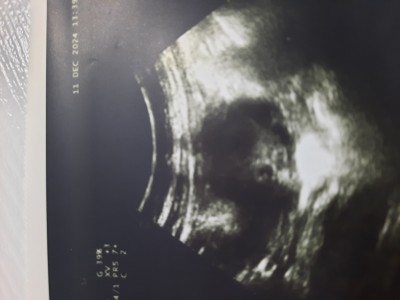

Hanimlar bugun dr gittim 2 hafta sonra gel kalp atisini dinlersin dedi ama kesede bebek yok gibi benmi goremiyorum dr da bise demedi 2 foto koyuyorum

Gebelik haftası 4+5

Kesen  çok  küçük  görünüyor  beta  hcg  kaçtı

Pazartesi istenisti 2248

Kese cok kucuk geldi bana da gerci dha yeni ama ne blim yaa

Daha çok küçük nu haftada bendede sadece boş kese görünüyordu

benim 5 haftalıkken beta 20.000 üzerindeyken bile böyleydi bir hafta sonra kalp atışını duyduk elhamdülillah korkulacak birşey yok